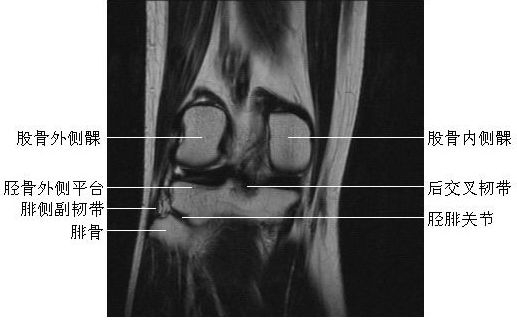

膝关节冠状面(一)

膝关节冠状面(二)